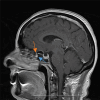

Cerebrospinal fluid (CSF) rhinorrhea is a relatively rare medical condition characterized by the drainage of CSF through the nasal cavity. Cerebrospinal fluid leakage can be attributed to a plethora of different causes, mostly traumatic or iatrogenic, but it can also be spontaneous. Due to its rare entity, CSF rhinorrhea is often a diagnostic trap and can be misdiagnosed and mistreated as rhinosinusitis or allergic rhinitis. This can result in severe complications, such as meningitis, which could potentially have life-threatening consequences if not accurately identified and managed. In this case report, a 53-year-old Caucasian woman presented at the emergency department with symptoms of headache, fever, transparent nasal discharge from her left nostril when leaning forward and mild neck stiffness. Based on the patient's clinical presentation and physical examination findings, there was a high suspicion of central nervous system infection and cerebrospinal fluid leakage. A lumbar puncture confirmed the diagnosis of meningitis, while imaging exams, including computed tomography (CT) and magnetic resonance imaging (MRI) scans, revealed a fistula between the posterior wall of sphenoid sinus and the subarachnoid space. Additional findings included an empty sella turcica, suggesting a potential underlying cause for this condition and an incidental meningioma near the area of leakage. The patient received empiric intravenous antibiotic therapy and was discharged after ten days. She was referred to the neurosurgical department for surgical repair of the CSF leak and removal of the meningioma, in line with appropriate treatment guidelines. This study highlights the importance of promptly identifying and thoroughly investigating potential causes of CSF leakage to provide appropriate medical management.